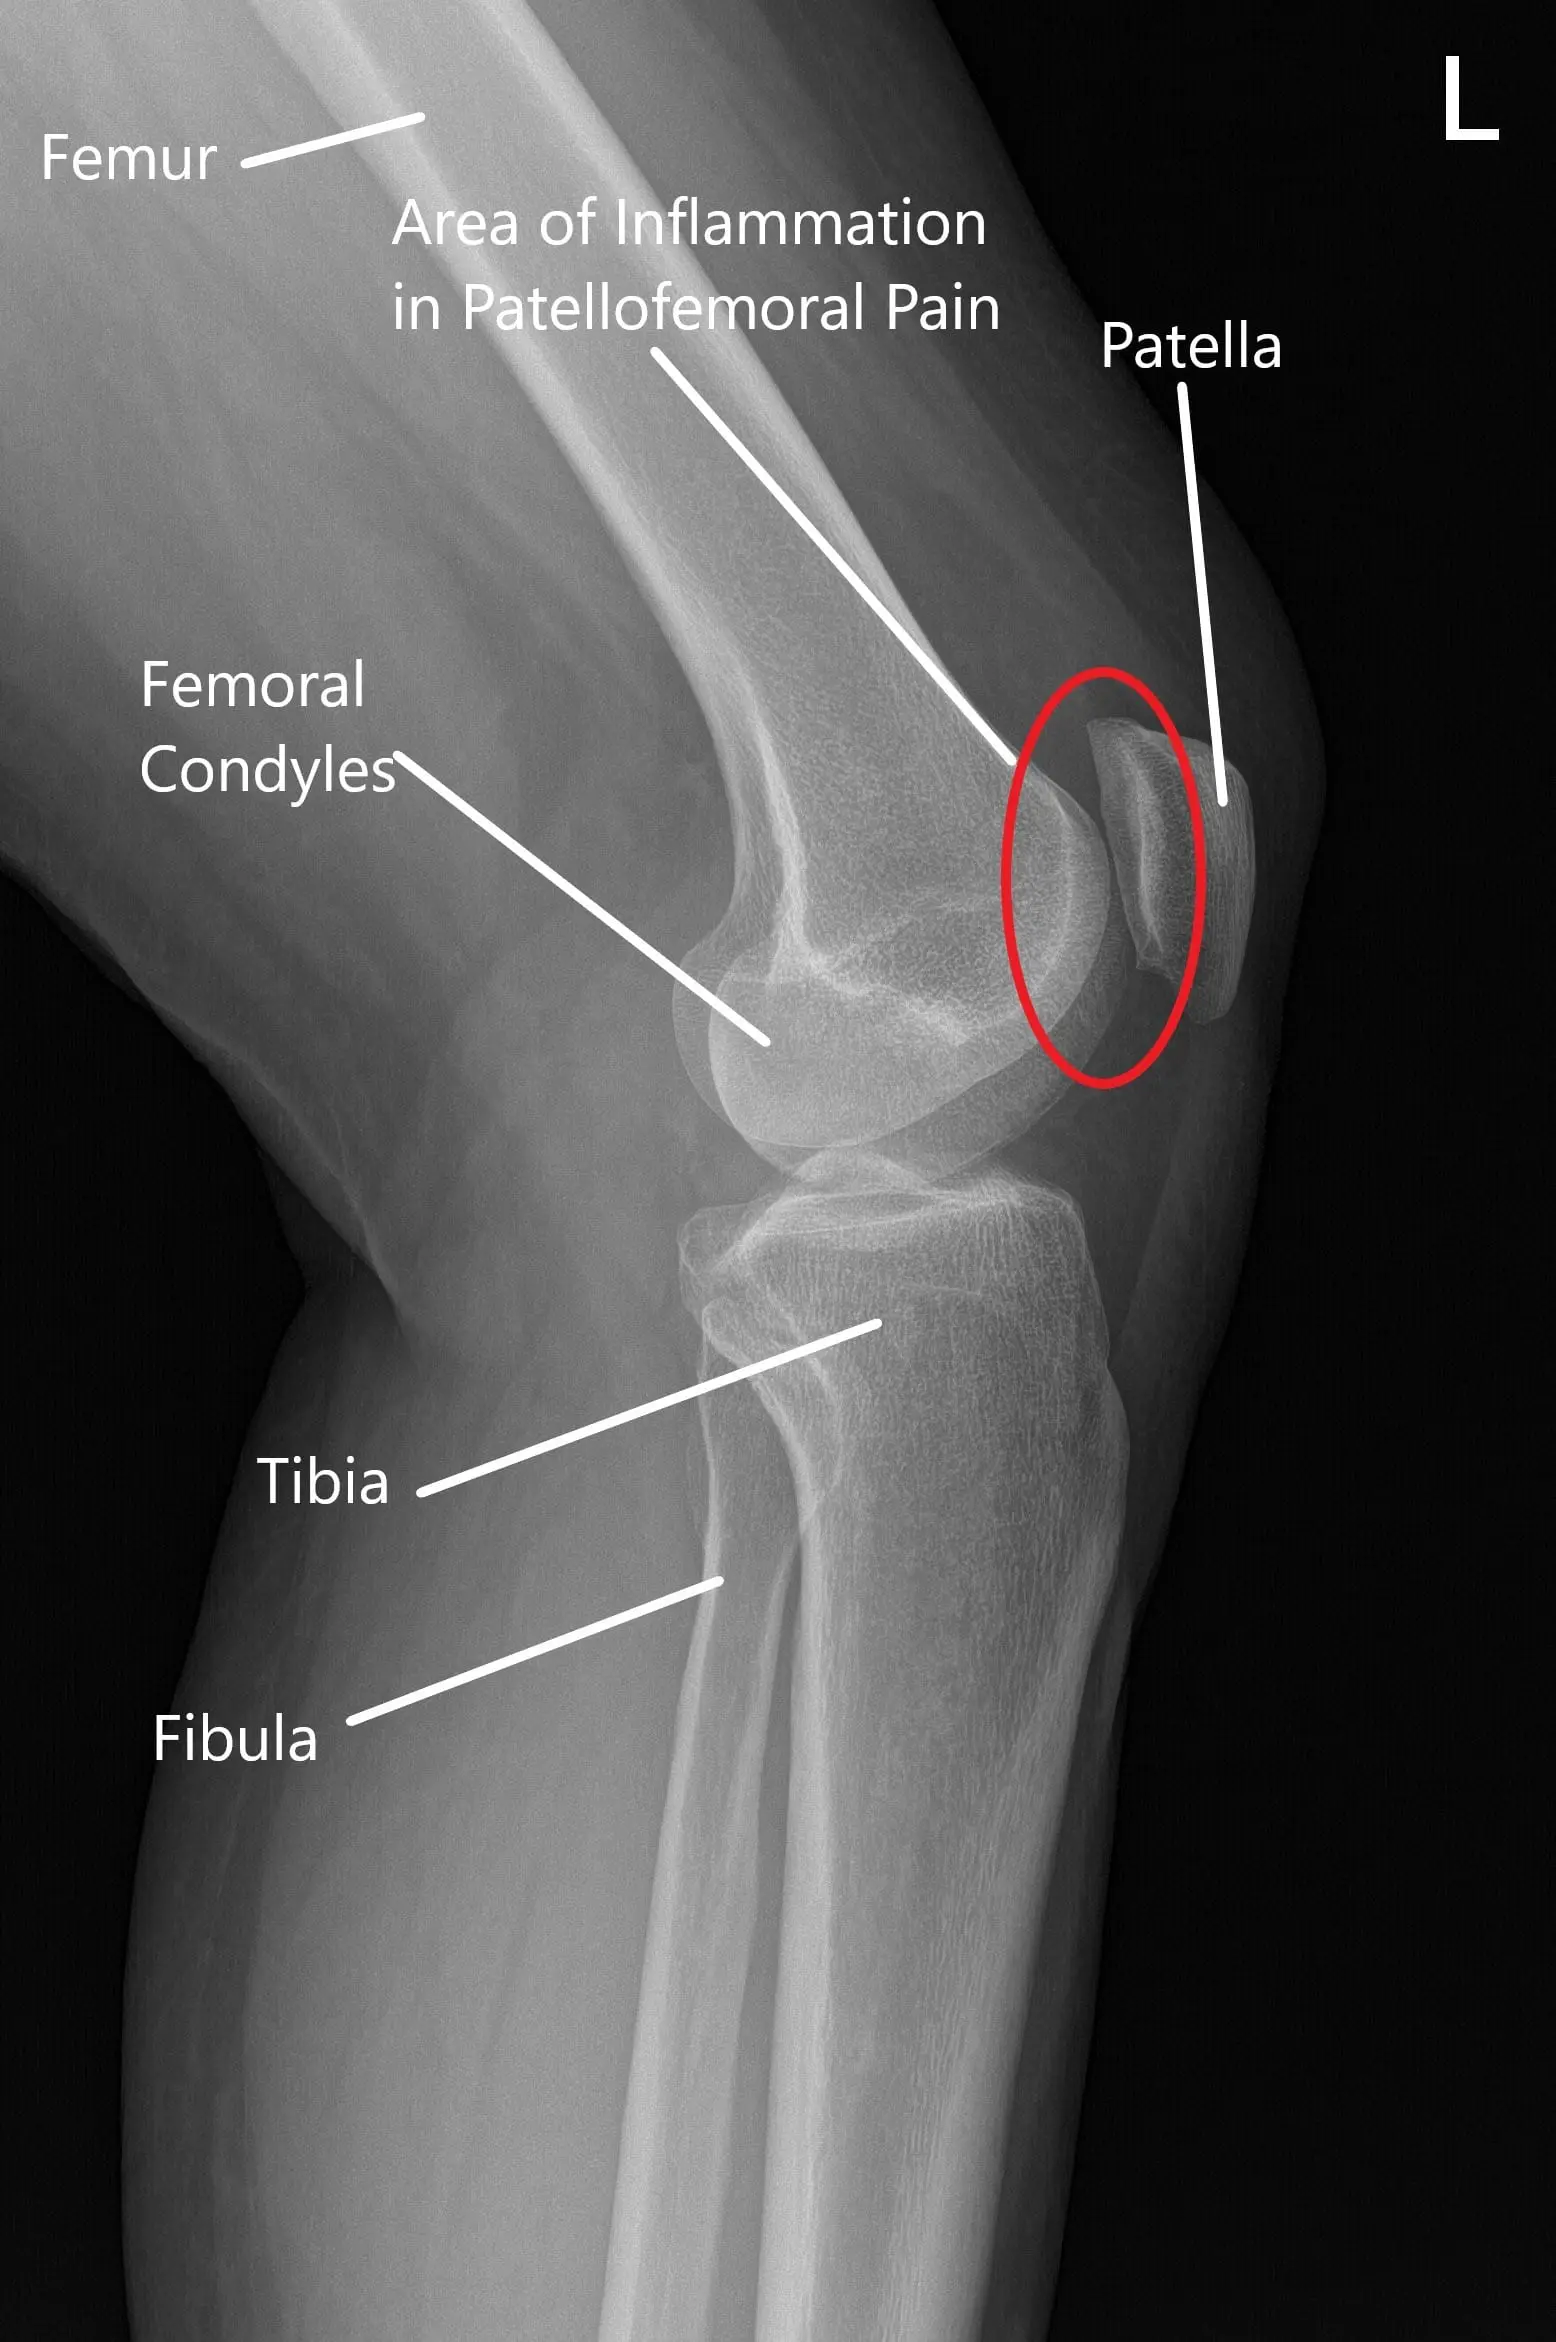

The patellofemoral joint is where the patella (kneecap) rests within the groove of the femur (thigh bone). The knee joint functions by allowing smooth bending and straightening movements, with the patella helping to stabilize and guide these motions. In PFPS, the alignment of the kneecap becomes compromised, often due to muscle imbalances, tight ligaments, or poor training, leading to pain and discomfort.

Normal X-ray of the knee joint showing the various structures in the Anteroposterior and Lateral view

Normal X-ray of the knee joint showing the various structures in the Anteroposterior and Lateral view.